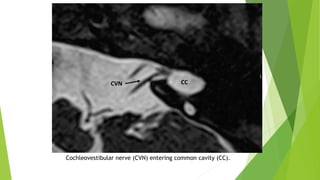

Correct terminology for the nerve entering the CC is common CVN.

CVN has to be demonstrated by 3 Tesla MRI in candidates undergoing

evaluation for CI candidacy.

In cases of CC CVN enters the cavity without separating into individual nerves.

Cochleovestibular nerve (CVN) entering common cavity (CC).

4- Normal CVN Normallycochlear and vestibular nerves originate at the brainstem together forming the CVN. CVN then separates into CN and superior and inferior vestibular nerves in the IAC. In cases of CC CVN enters the cavity without separating into individual nerves. if the size is 1.5-2 times as much as the ipsilateral FN or similar to contralateral normal CVN it can be accepted as normal.

Cochleovestibular nerve (CVN)entering common cavity (CC).